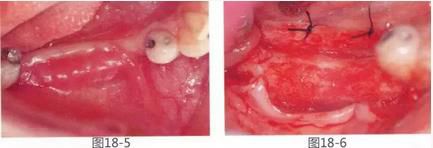

圖18-5  術(shù)后1個(gè)月的狀態(tài)??梢钥吹礁材ぢ冻?。

圖18-6  術(shù)后月1年。獲得充分寬度的牙槽嵴。